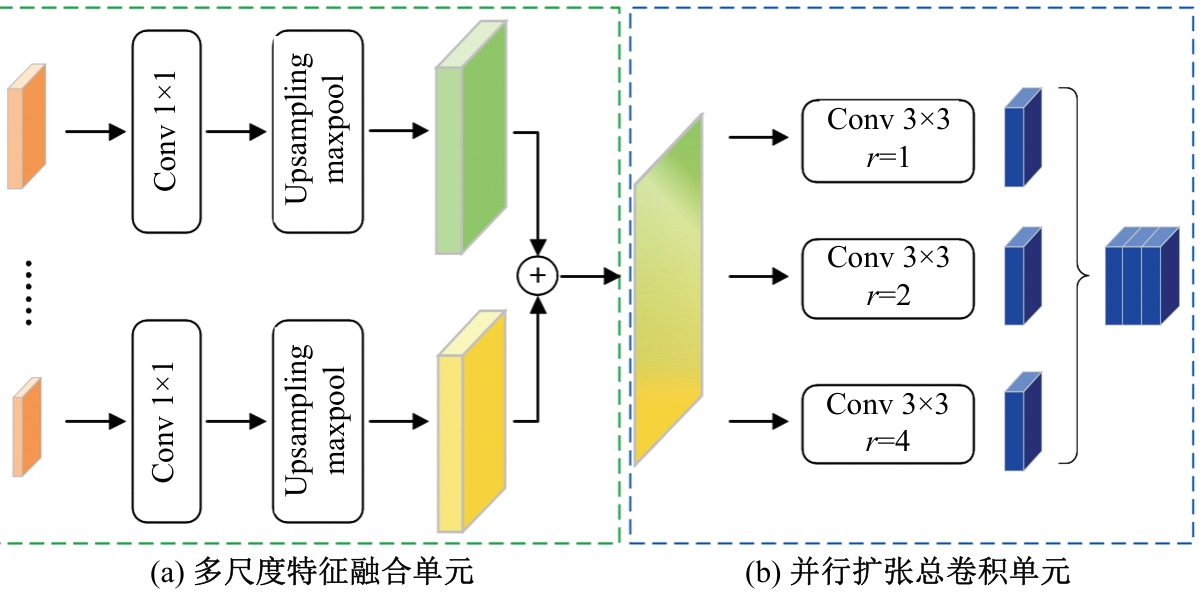

针对脑皮层下组织部分结构(如纹状体)在医学影像中目标小、对比度低,图像分割难度大,在自动医学诊断中应用比较困难的问题,本文基于深度学习的方法提出了一种医学图像分割网络,在磁共振成像中分割组成纹状体的苍白球、尾状核、壳核3部分。本文提出的网络模型具有捕获全局和局部特征的能力,并建立了全局与局部信息的相关性,在深度不退化的同时有效融合不同尺度的深层语义特征和浅层细节特征,实现对纹状体的精确分割。模型在公开的脑部数据集上进行了验证,并与其他先进的方法进行对比,结果表明本文的戴斯相似系数、平均交并比、95%豪斯多夫距离分别为94.26%、90.94%、3.82,均优于其他几种方法,达到了先进水平,这表明本文模型可以提高对纹状体的分割精度,为相关疾病的研究提供依据。